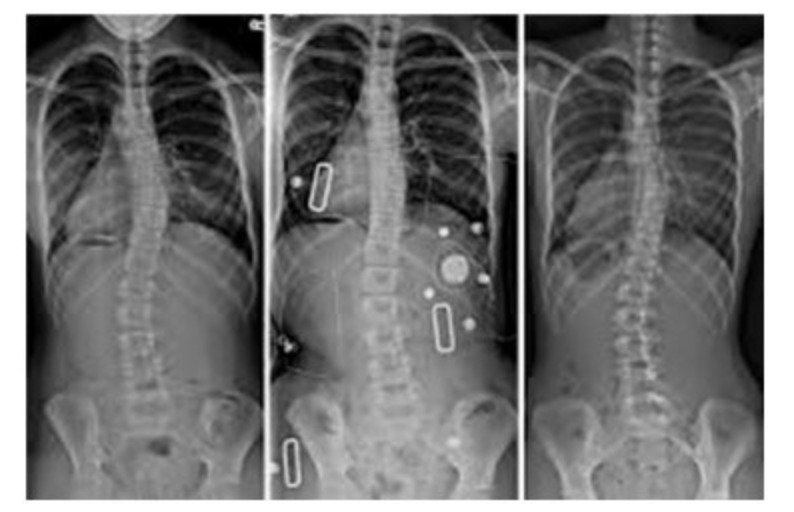

Restoring the human frame to Orthogonal and Tensegral has become quite the task. For over a hundred years chiropractic was the only…

The objective of the Upper Cervical (UC) spinal correction has always been about directing force into the body in an effort to move a…